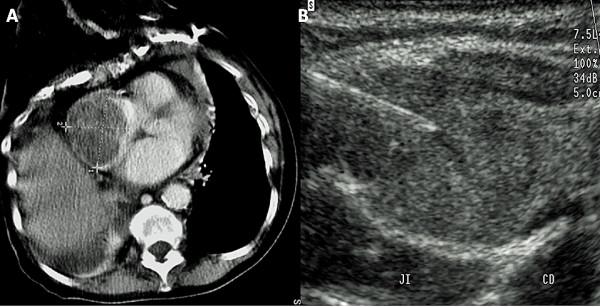

Of 1171 patients with thyroid cancer treated at our institution over the last 18 years, we retrospectively identified nine patients (0.8%), three women and six men, aged 34-81 years (median age: 70 years) presenting with malignant thyroid tumor of median diameter 45 mm (range: 23-87) having venous obstruction of thyroid malignancy origin. Two patients underwent multimodal therapy. All other patients underwent external beam radiation therapy alone +/- chemotherapy or palliative care. Ultrasound (US) provided particularly useful information on venous involvement characteristics. Median survival was 7 months and median progression-free survival was 6 months. Survival in our series was worse than that of previously reported series despite diagnosis of vein involvement at an early stage in 2/3 cases using US.

Despite small numbers of patients, it seems that aggressive treatment modalities including surgery are required to improve survival. In our experience, US was a useful non-invasive method to describe tumor extensions to great veins of the neck (invasion versus compression, tumor thrombus versus blood clot) and should be recommended to depict early venous invasion in cases of suspected thyroid malignancy.